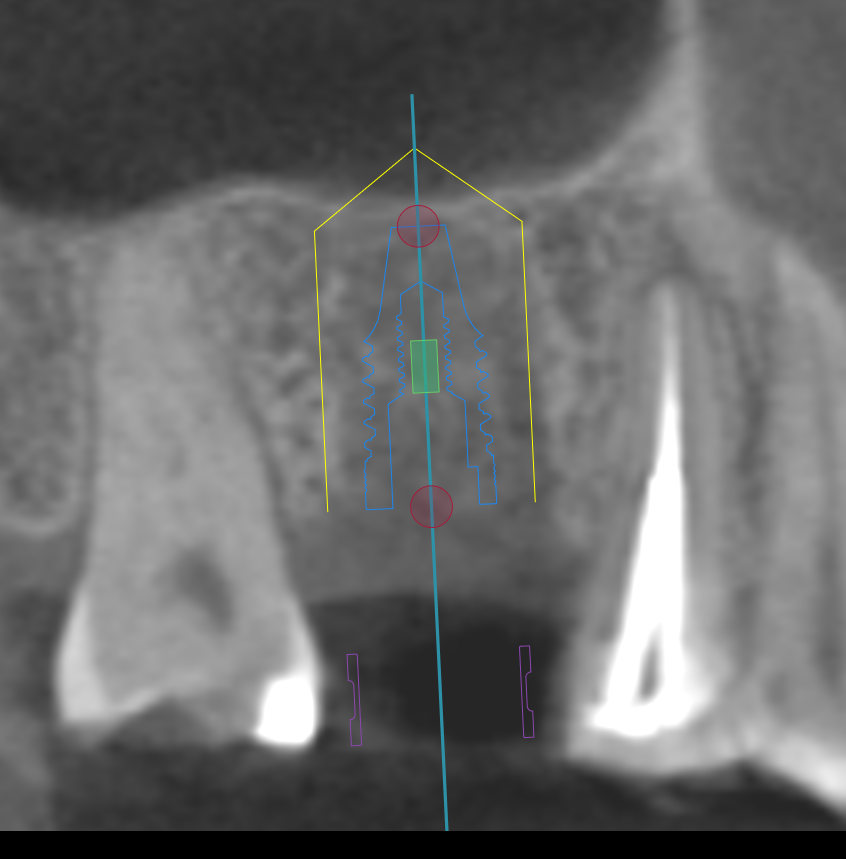

CT撮影

埋入位置を決めるための装置(ラジオグラフィックガイド)を口腔内に入れCTを撮影します。

CTシミュレーション

CTデータをインプラント解析ソフトに入れ、手術のシミュレーションをします。

・骨の状態を確認し、骨造成が必要か見極めます。

・シミュレーションでインプラントが可能か確認し、インプラントのサイズを調べます。